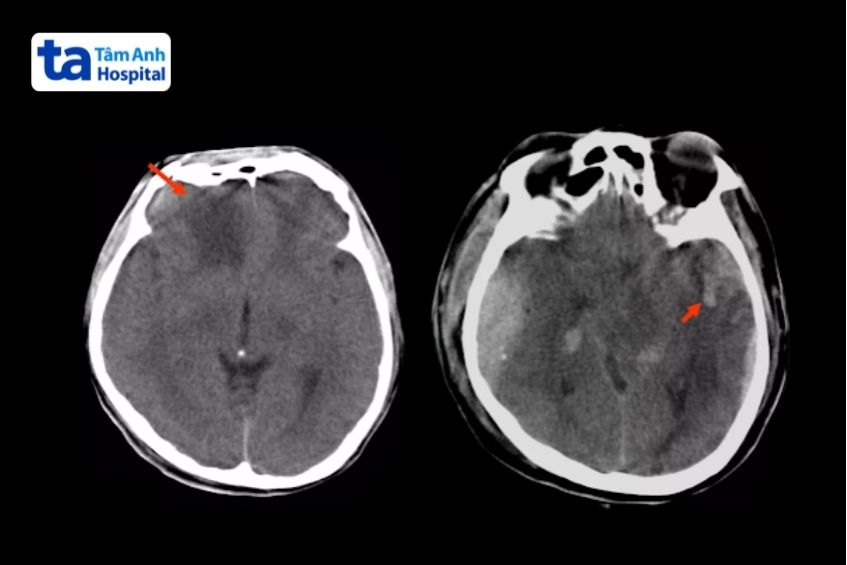

Dập não xuất hiện trên CT là một vùng giảm tỷ trọng do phù nề, xen kẽ các điểm tăng tỷ trọng của ổ xuất huyết. Vùng tổn thương thường gây hiệu ứng choán chỗ vì phù não lan rộng. Nguyên nhân chủ yếu do chảy máu trong nhu mô não tại khu vực gần xương sọ, nơi chịu tác động va đập. Tuy nhiên, đôi khi tổn thương lại xuất hiện ở phía đối diện với chỗ va đập, do lực phản hồi trong quá trình chấn thương.

Ảnh chụp CT phát hiện dập não do chấn thương